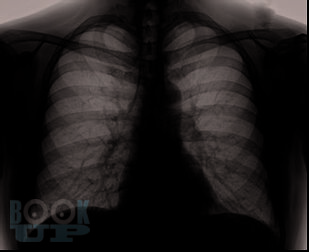

Хроническая обструктивная болезнь легких в амбулаторной практике: дифференциальная диагностика, тактика ведения больных

Хроническая обструктивная болезнь легких является одной из ведущих причин инвалидности и смертности населения.

В данном учебном пособии отображены основные критерии клиники и диагностики больных с патологией бронхолегочной системы. Подробно рассмотрены ведущие симптомы, которые встречаются у больного с ХОБЛ и требуют необходимости дифференциальной диагностики уже на амбулаторном приеме у врача-терапевта, отображены особенности течения заболевания, представлены алгоритм проведения дифференциальной диагностики заболевания и необходимый перечень обследования пациента в амбулаторных условиях. Разобрана тактика лечения больного с ХОБЛ в условиях первичного звена здравоохранения. Представлен раздел с тестовыми заданиями и клиническими задачами для самостоятельной работы.